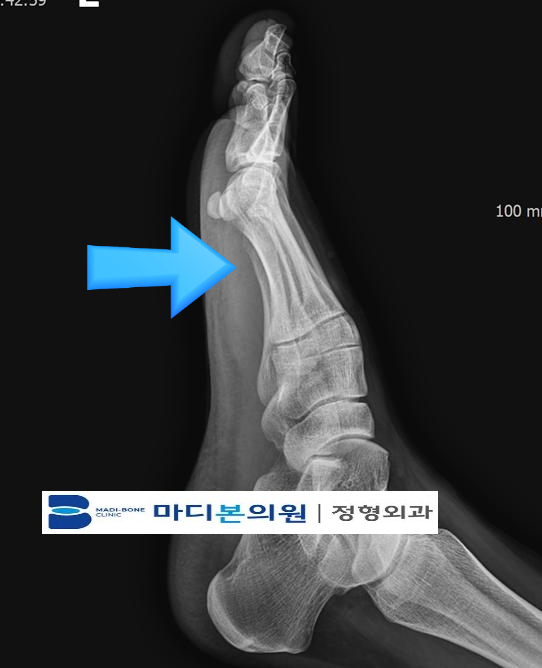

In many cases, an X-ray is performed to evaluate bone alignment and rule out other conditions.

Imaging helps clinicians differentiate between midportion tendinopathy, insertional tendinopathy, and other causes of heel pain.

Achilles Imaging Review